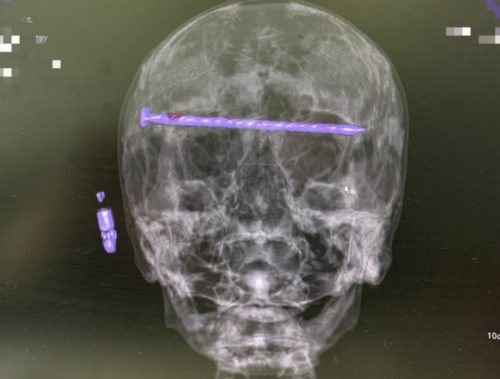

Сложная операция в Нижнем Тагиле: врачи извлекли гвоздь из головы пациента

78-летний мужчина успешно перенёс экстренное хирургическое вмешательство.

Нижнетагильские врачи в результате сложнейшей операции достали из головы 78-летнего пациента 15-сантиметровый гвоздь.

Мужчина поступил в приёмный покой Городской больницы №1 Нижнего Тагила в тяжёлом состоянии. На КТ медики увидели в костях черепа гвоздь, который прошёл через обе глазницы от правого до левого виска. Длина его достигала 15 сантиметров. Ситуация осложнялась повреждением твёрдой оболочки мозга и сдавлением глазных яблок.

Чтобы спасти пациента, бригада специалистов во главе с заведующим нейрохирургическим отделением ГБ №1 Нижнего Тагила Дмитрием Неволиным провела экстренную операцию. Гвоздь извлекли, сохранив мужчине и жизнь, и зрение.

Прооперированный мужчина под наблюдением бригады врачей быстро восстанавливается. Для профилактики осложнений он проходит антибактериальную терапию.